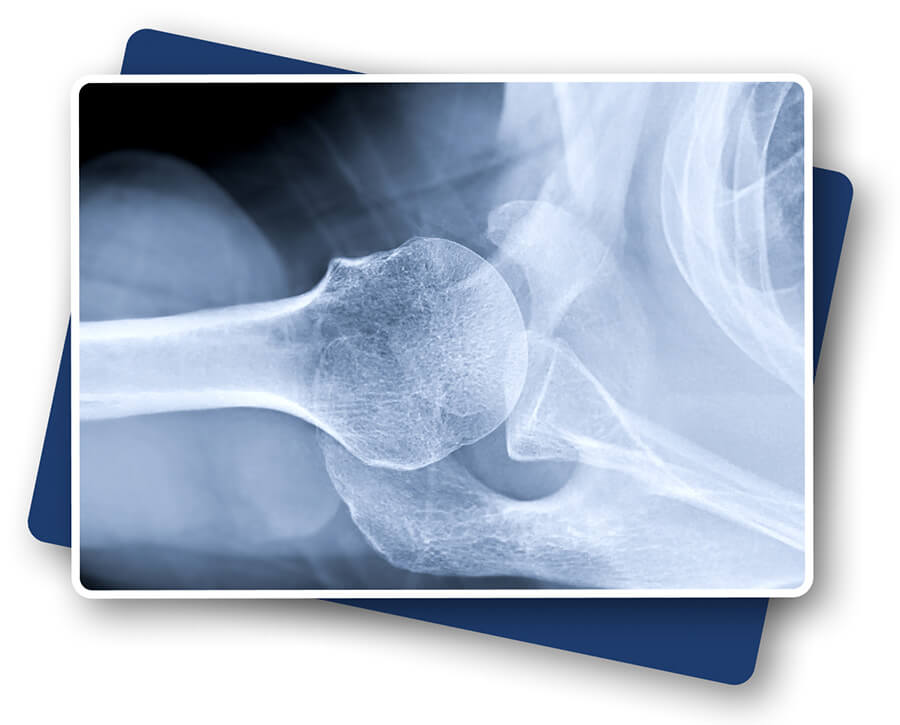

Radiologues

Médecin spécialisé dans l'imagerie médicale, qui interprète les radiographies, IRM, scanners et échographies pour diagnostiquer des pathologies.